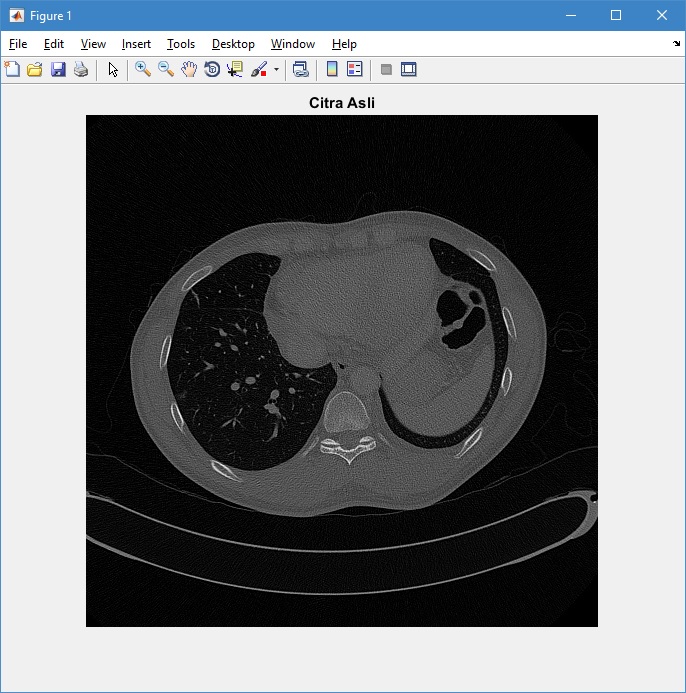

Pengolahan Citra CT Scan Paru-Paru dengan Metode Segmentasi Active Contour

Penelitian mengenai pengolahan citra medis telah banyak dilakukan dengan mengembangkan berbagai macam metode pengolahan citra. Penelitian yang dilakukan di antaranya bertujuan untuk meningkatkan kualitas citra agar citra lebih mudah diinterpretasi dan untuk menganalisis citra secara objektif. Berikut ini merupakan contoh aplikasi pemrograman MATLAB untuk melakukan pengolahan citra CT Scan Paru-Paru dengan metode segmentasi active contour. Citra diakuisisi dengan modalitas pesawat CT Scan berformat DICOM (Digital Imaging and Communications in Medicine). Pengolahan citra dilakukan untuk menghitung luas dan keliling daerah paru-paru.

1. Membaca citra asli

clc; clear; close all; warning off all;

Img = dicomread('1');

figure,imshow(Img,[])

title('Citra Asli')